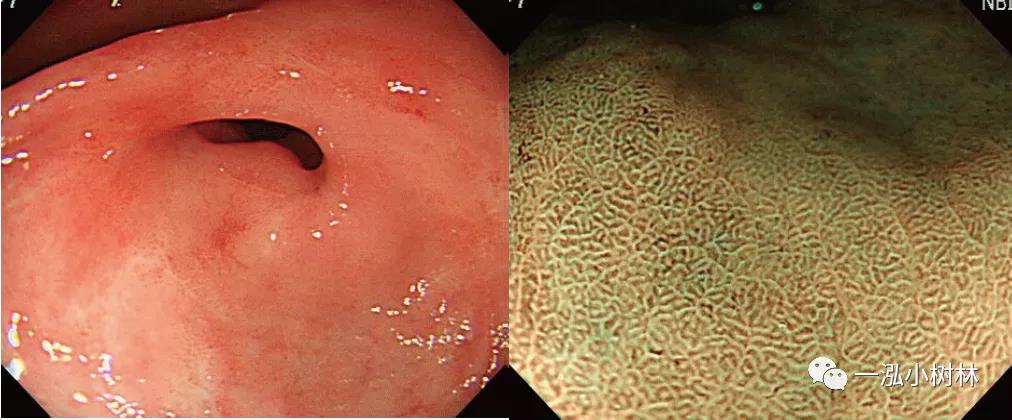

例2 16岁女性患者,嗜酸粒细胞性胃肠炎

图2 嗜酸粒细胞性胃肠炎. 内镜:大肠黏膜水肿;病理:嗜酸性粒细胞性胃肠炎病例的大肠活检组织像.黏膜固有层可见多个嗜酸性粒细胞的浸润.